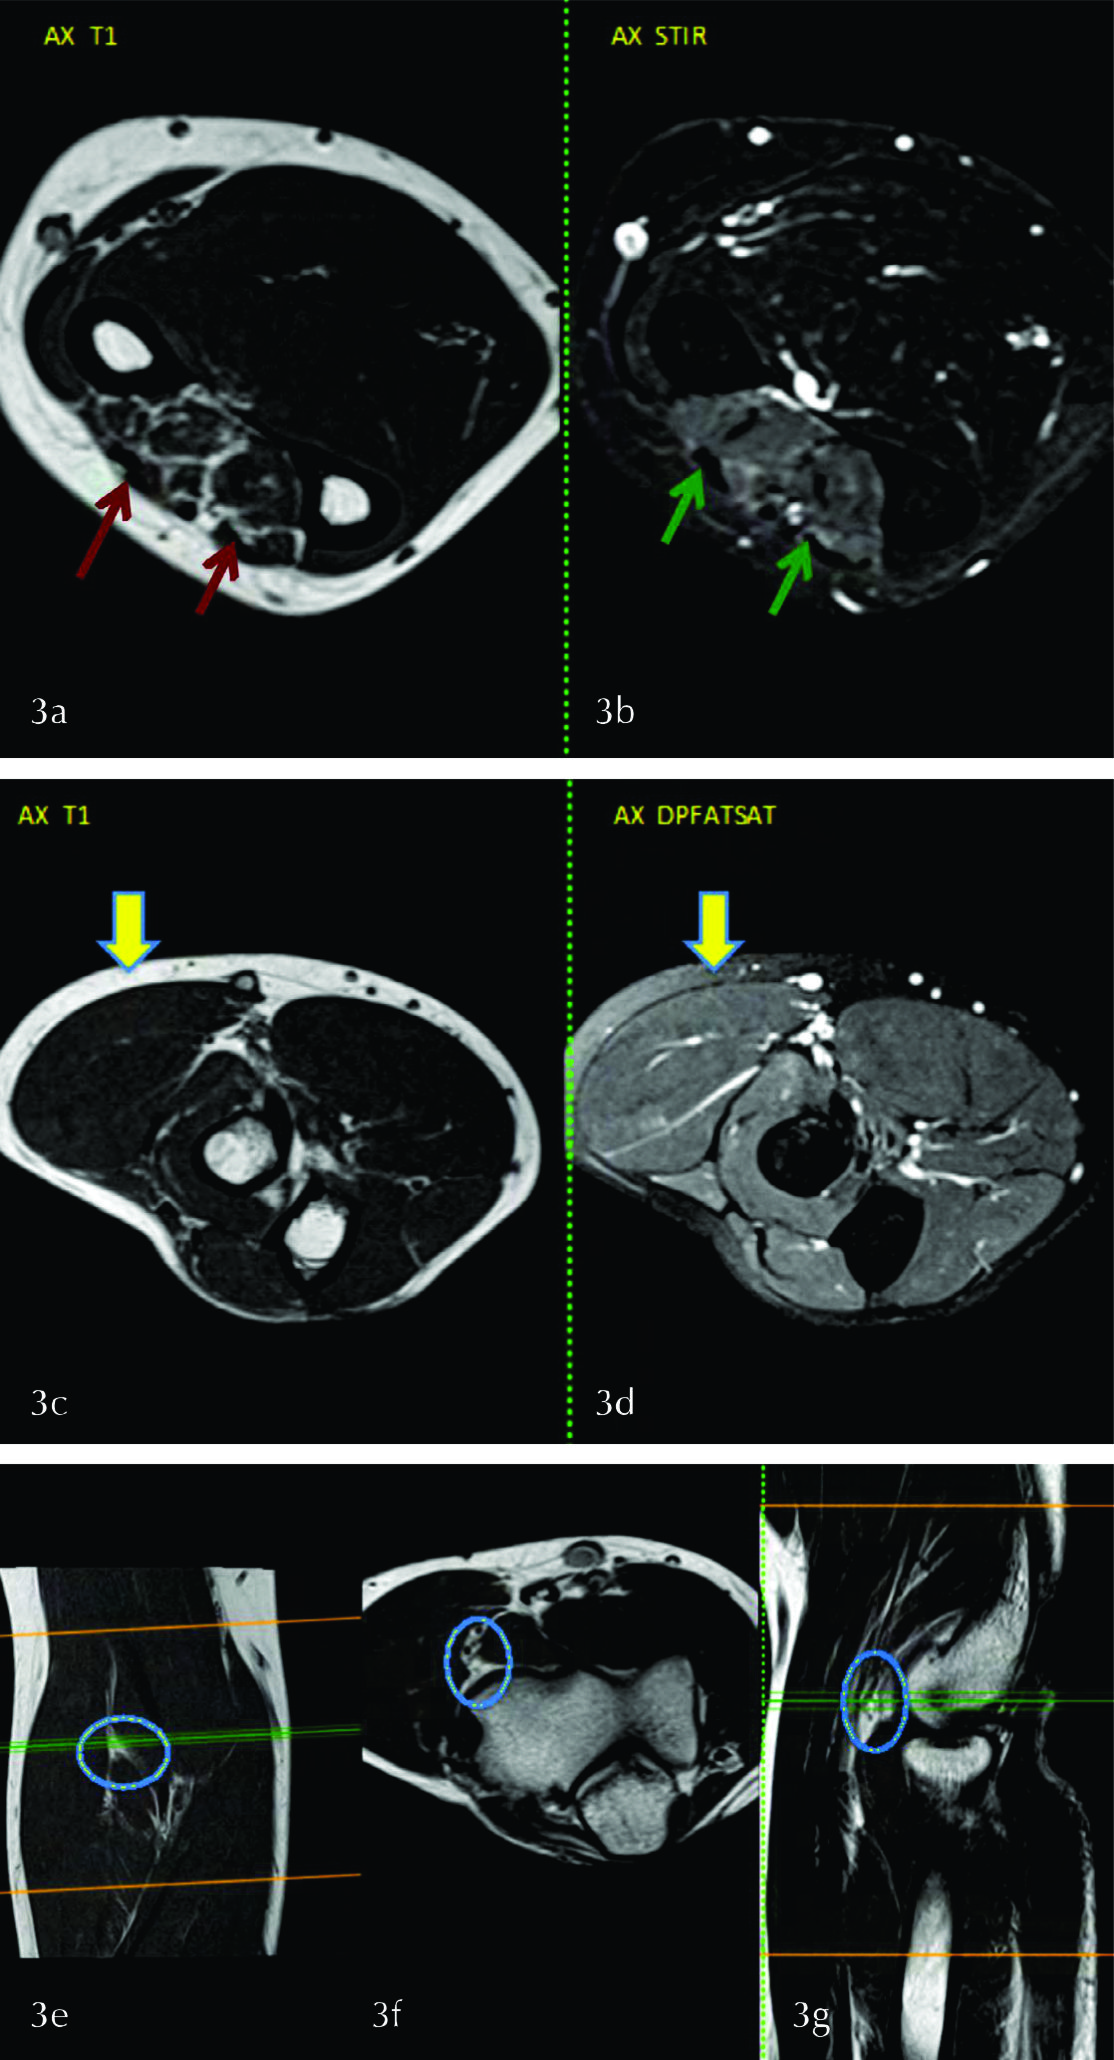

Paciente de 31 años, SM, al que se le solicita una RM de antebrazo por clínica que orienta a afectación de nervio radial. En la misma se evidencia edema de músculos extensores (cubital del carpo, largo del pulgar, de los dedos y del meñique) y abductor del pulgar (fig. 3 a) asociado a signos de atrofia de los mismos visualizada en T1 (fig. 3b). De acuerdo al territorio afectado corresponde a una neuropatía del nervio radial.

En el tercio superior de antebrazo (fig. 3 , c y d) se observa que están preservados los músculos braquioradial y extensores radiales del carpo cuya inervación depende de ramas proximales del mismo nervio lo cual orienta a atrapamiento de la rama interósea posterior.

El atrapamiento de la rama interósea posterior del nervio radial ocurre con mayor frecuencia a nivel del túnel radial, particularmente en relación con el borde proximal de la cabeza superficial del supinador, que puede formar hasta en el 30% de los individuos un arcada fibrosa o de Frohse. En la figura 3 (e, f y g) se visualiza en éste paciente el nervio radial en la topografía de la arcada de Frohse, donde no se identificaron causas compresivas.

Figura 3

Imágenes axiales a nivel del tercio medio del antebrazo donde se identifica edema en secuencia STIR de los músculos del compartimiento extensor (flechas verdes en b) y atrofia de los mismos en T1 (flechas rojas en a). En c y d, a la altura del tercio distal de codo, se observa preservación de los planos musculares extensores (flechas amarillas). En e, f y g, imágenes en T1 en los planos axial y sagital, se muestra la arcada de Frohse y la rama profunda del nervio radial (círculo).